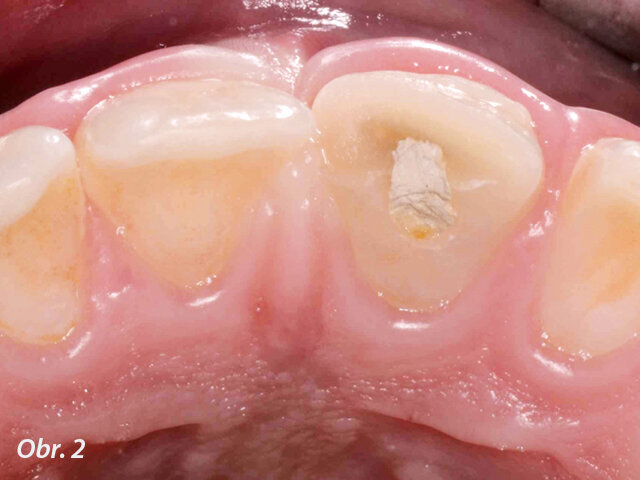

Při klinickém vyšetření nacházíme sanovaný smíšený chrup odpovídající věku pacienta. Zub 11 je poklepově a palpačně nebolestivý, parodontální sondáž je v mezích fyziologické normy. Z vestibulárního pohledu tvarově a velikostně odpovídá kontralaterálnímu zubu (obr. 1), z okluzního pohledu je vestibuloorální rozměr nepatrně větší než u zubu 21 (obr. 2). Šikmá fraktura zubu 11 má meziální okraj cca 1 mm nad okrajem marginální gingivy a distálně zasahuje do incizální třetiny klinické korunky. Dle diagnostického intraorálního rentgenového snímku je ukončen vývoj kořene s přítomným periapikálním nálezem a projasněním na meziálním aspektu kořene. Na ortoradiálním intraorálním rentgenovém snímku, ve srovnání se zubem 21 není jasně zřetelný průběh kořenového kanálku (obr. 3) a na excentrickém rentgenovém snímku je viditelný náznak kontury druhého kořene (obr. 4).